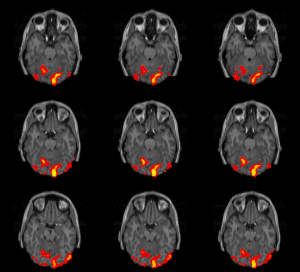

Eine Studie aus 2016 konnte mit Hilfe von fMRT-Untersuchungen zeigen, dass bei Menschen mit ASMR-Empfindungen eine verstärkte Verbindung bestimmter Hirnareale vorliegt. Bei diesen Hirnregionen handelt es sich vor allem um solche, die während des Nichtstuns aktiv werden[48] (Symbolbild).

Eine weitere Studie des Jahres 2016 wies unter Einsatz von fMRT-Untersuchungen darauf hin, dass bei Menschen mit ASMR-Wahrnehmungen eine verstärkte Konnektivität bestimmter Default-Mode-Networks (DMN) vorliegt.[50] Bei DMN handelt es sich um eine Gruppe von Gehirnregionen, die beim Nichtstun aktiv werden und beim Lösen von Aufgaben deaktiviert werden, darunter der mediale präfrontale Cortex, Praecuneus, Teile des Gyrus cinguli sowie der Lobuls parietalis superior des Scheitellappens.[51] Die Autoren schlussfolgern, dass diese atypische Konnektivität der Gehirnregionen an den ASMR-Empfindungen beteiligt sein könnte.